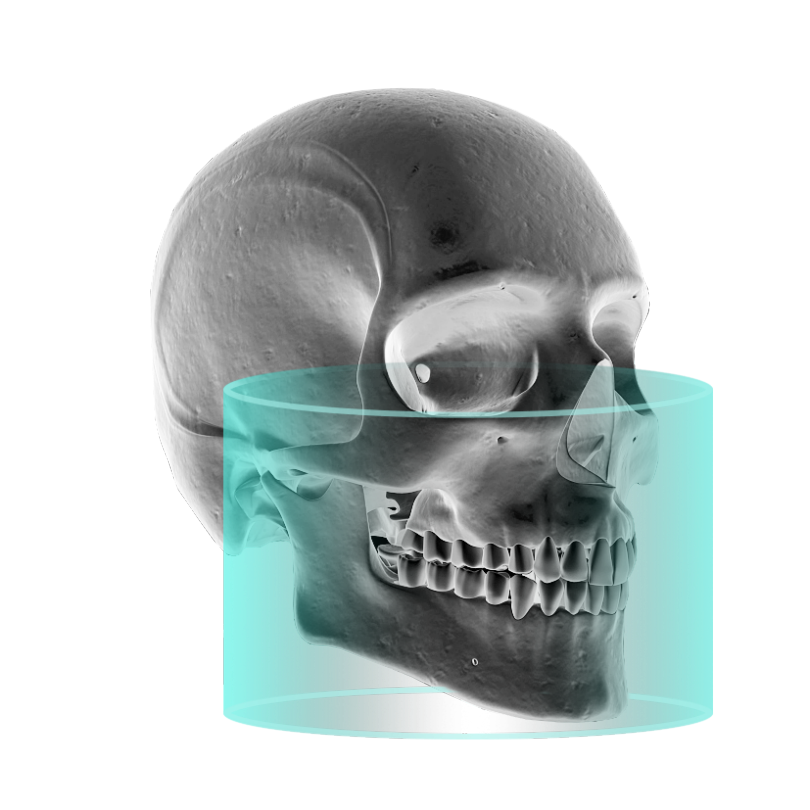

黄金FOV

14cm * 10cm

14cm为圆柱体直径,10cm为圆柱体高度,

FOV决定着单次成像将包含住多少有口腔临床意义的解剖信息

亚洲人左右颞下颌关节远中点距离通常在12.5cm左右,但因为颞下颌关节通常不在成像圆柱体的直径上,所以需要至少13cm的水平直径范围才能将左右颞下颌关节的全部解剖结构囊括在同一个CT影像上,而考虑到极个别患者的个体差异和摆位的误差,菲森选择了直径:

14cm的视野范围以确保万无一失;

同时,为了满足下颌下缘到颞下颌关节垂直距离通常在9cm的亚洲人体质,菲森特意选取了10cm的高度范围,以保证单次投照即可获得上颌窦全部和颞下颌关节全部。